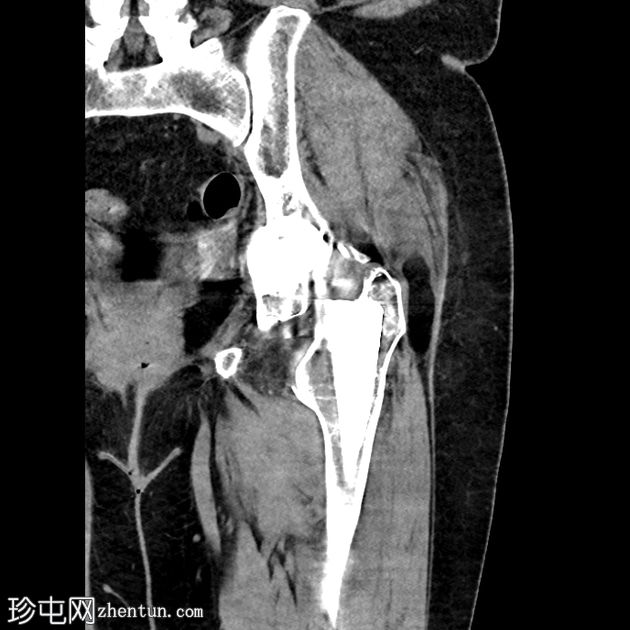

X线片

正位片

双侧全髋关节置换术假体完整,无松动迹象。

左侧股骨大转子下区外侧皮质中断,侧位片显示最佳,提示假体周围骨折。